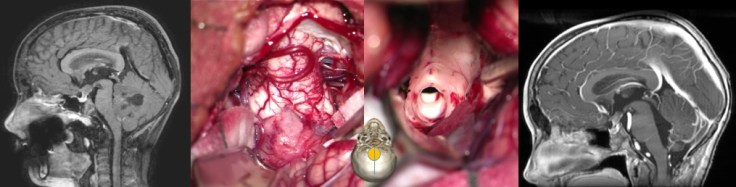

prise en charge chirurgicale

traitement de l’hydrocéphalie

le plus souvent, on réalise en urgence une ventriculocisternostomie endoscopique ; ceci permet de mettre le patient à l’abri du risque d’engagement et de lésion des nerfs optiques, mais ne résout pas le problème de la compression du tronc cérébral.

la chirurgie a pour but une résection si possible totale de la lésion ; en cas de reliquat postopératoire accessible, un second look est à discuter.

il s’agit d’une chirurgie lourde, avec une morbidité liée à la localisation tumorale : la chirurgie du médulloblastome est le plus grand pourvoyeurs des tableaux de mutisme cérébelleux.